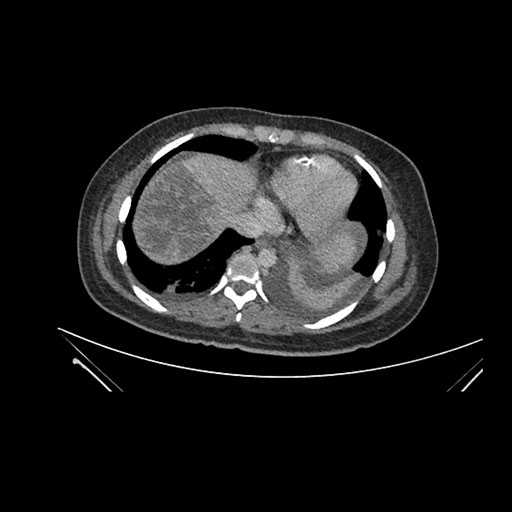

Imaging Analysis

Look through the patient's CT scan to identify any areas of concern for the necessary procedure.

Axial Venous

Based on initial findings, which issue(s) would you be most concerned about?